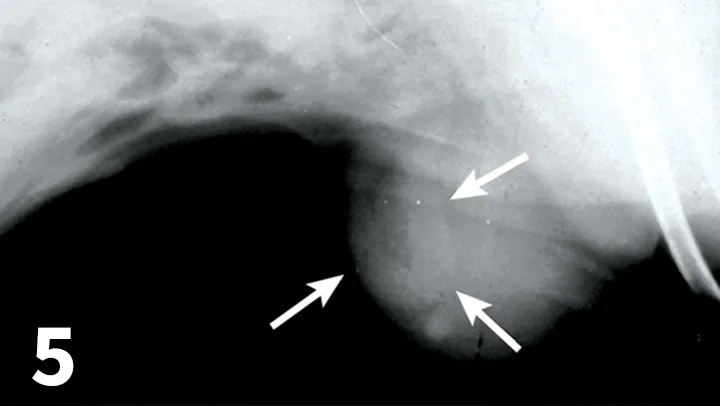

Featured Image

FIGURE 5

Lateral radiographic view showing tubular organ displacement into the subcutaneous tissues (arrows) from a ventral incisional hernia.

Imaging

• Plain films showing abdominal organ displacement into subcutaneous tissue at the wound site are diagnostic for an incisional hernia (Figure 5).

• Often the nature of soft tissue swelling outside the abdominal wall closure site cannot be defined clearly on plain films.